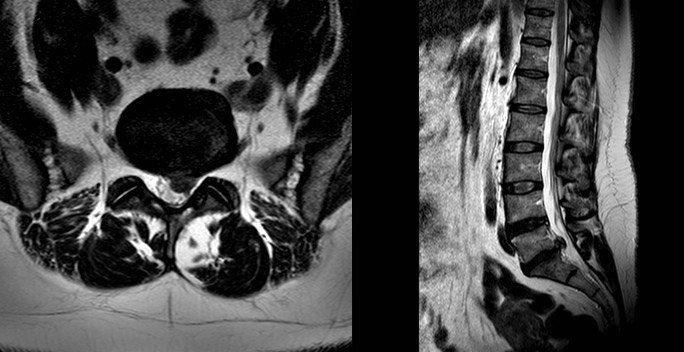

When do I need a re-scan?

The images below show a resolved disc prolapse. There is no longer black material in the spinal canal. Whether you need a new scan will depend on how you respond to treatment, clinical assessment and if it is felt you may benefit from an operation.

Can my disc prolapse heal itself?

Yes. The body has a remarkable capacity for repair. This prolapse resolved within 3 months. The body shrinks the disc by absorbing water, when this process is complete your pain will improve. The majority of discs will improve given long enough. My role is to guide you through the options, and step in if your life is on hold and waiting is unacceptable you may be a candidate for surgery on the lower back.